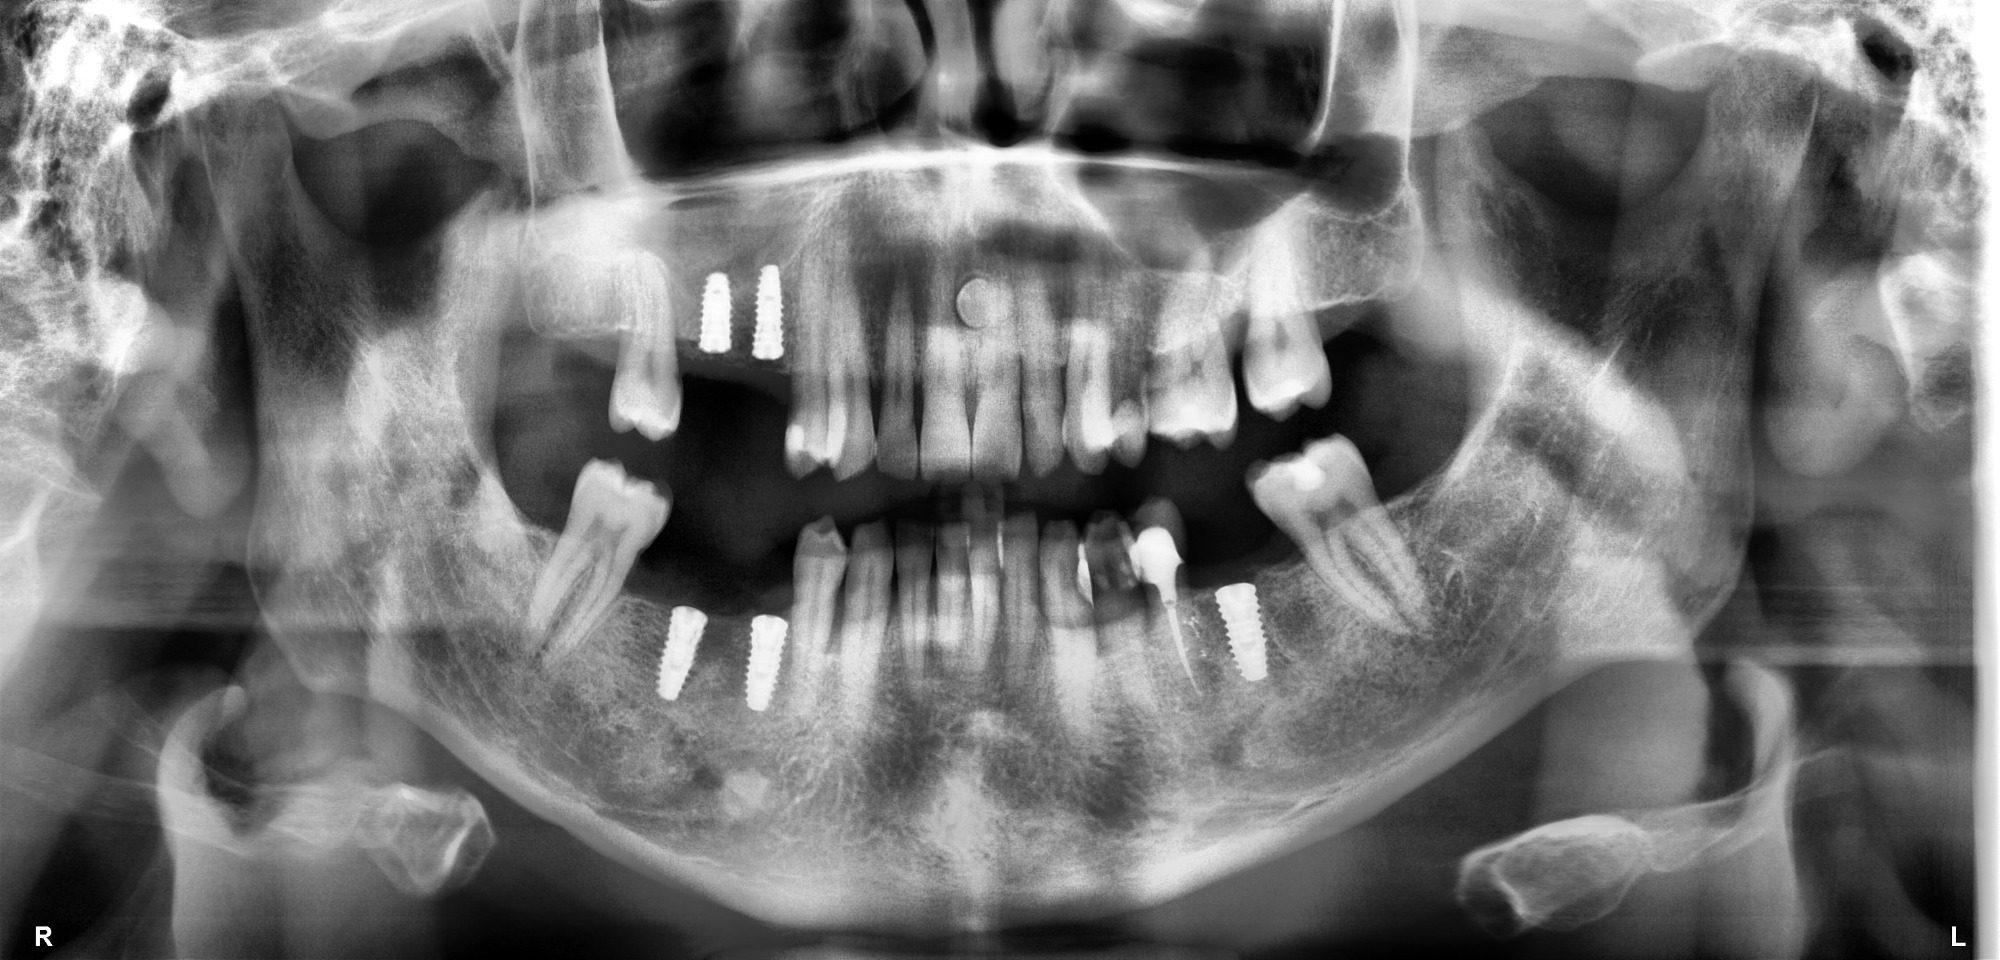

Transformamos la experiencia clínica dental sin apuros, sin suposiciones y sin esperas innecesarias. Nuestro equipo de especialistas utiliza tecnología CEREC 3D, escáner intraoral, pabellón quirúrgico autorizado y planificación digital para resolver tus necesidades en una sola sesión. Agenda hoy tu evaluación personalizada.

Con el sistema CEREC fabricamos tus restauraciones cerámicas directamente en clínica, eliminando laboratorios externos y semanas de espera. Entras con un problema, sales con una solución definitiva.